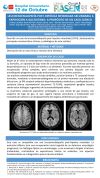

Embolismo paradójico. Utilidad del doppler en neurología